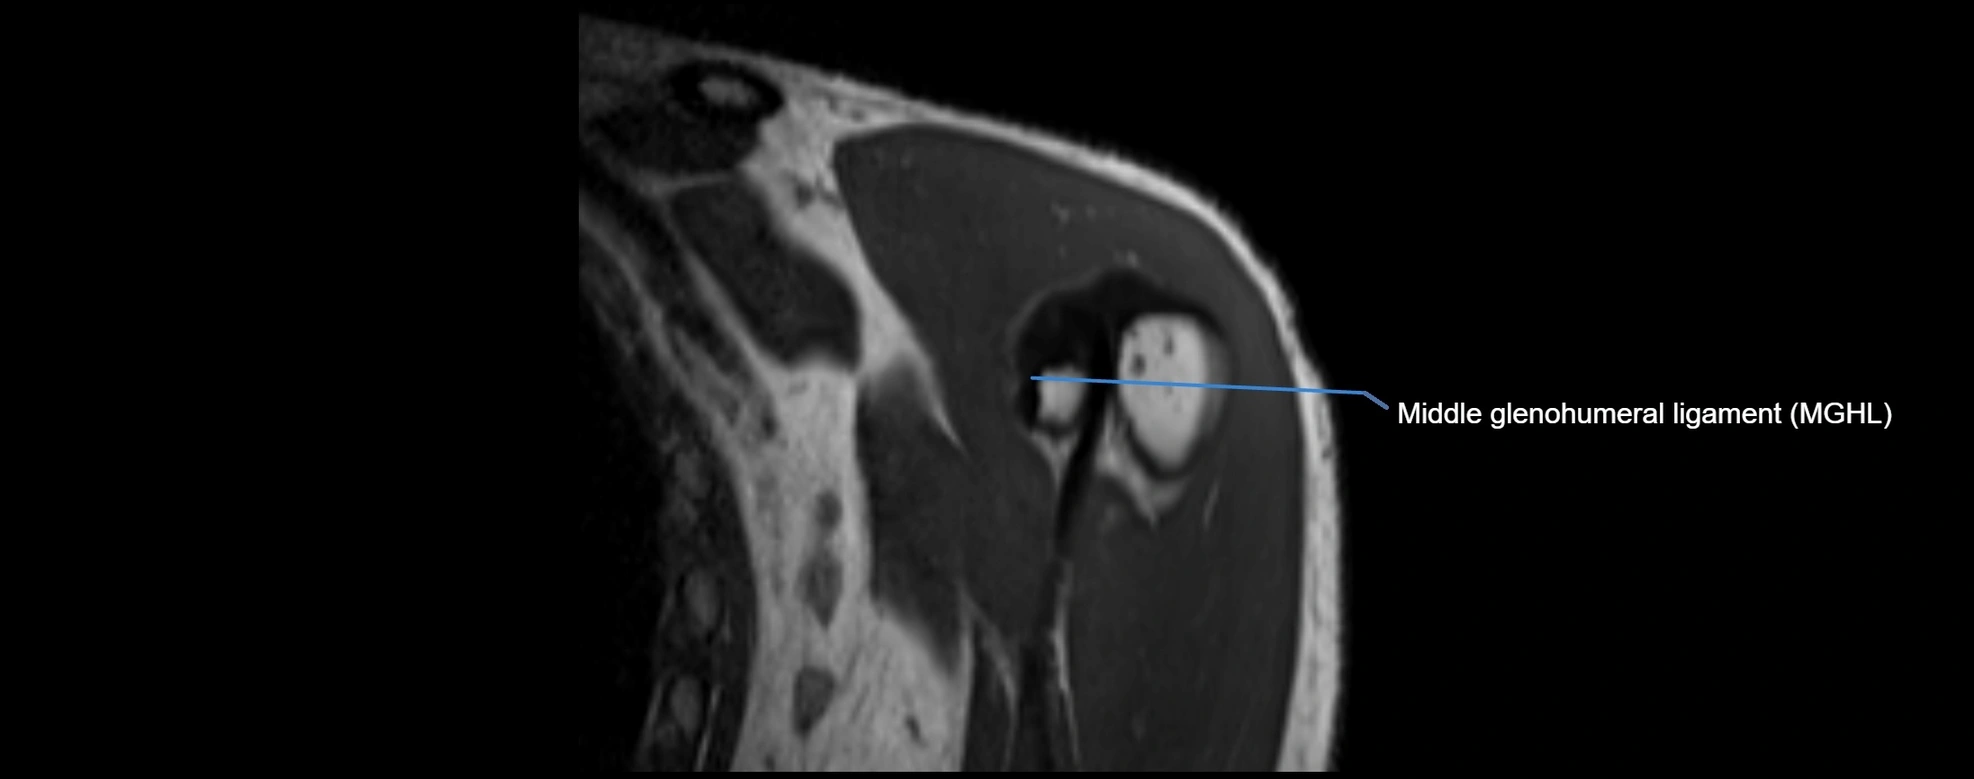

MRI images

image